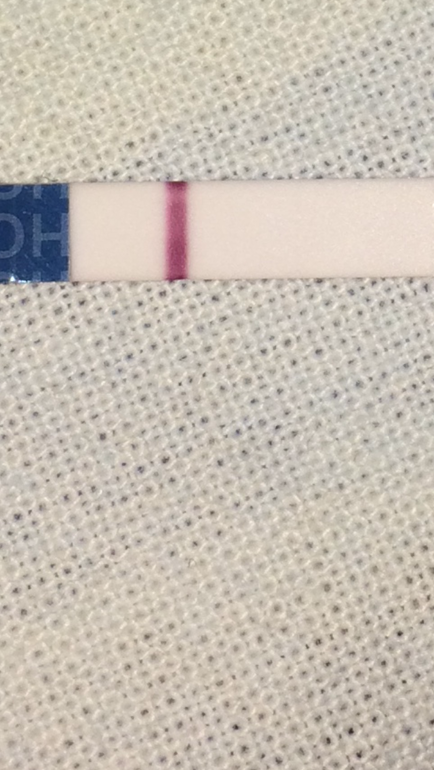

Девочки, сегодня 20 д. ц. , цикл 25-27 дней, первый цикл на дюфастоне с 10 по 25 д. ц. Честно говоря особо не надеялась, да и рано наверно ещё, но что то вдруг подтолкнуло и я зашла в аптеку)).

Девочки, сегодня 20 д. ц. , цикл 25-27 дней, первый цикл на дюфастоне с 10 по 25 д. ц. Честно говоря особо не надеялась, да и рано наверно ещё, но что то вдруг подтолкнуло и я зашла в аптеку)).

Я вроде видела, когда сырая была, но подсохла и исчезла, через день повторю, особо конечно не надеюсь, начиталась про дюф что до овули нельзя, но решила следовать рекомендации врача, в след цикл буду отслеживать и бт мерить, до месячных ещё неделя, может быть ещё рано тесты мочить, да и живот тянет как перед ними..

И главное её было видно сразу как намокла, когда высохла не видно.

Когда фото приближаю контуры видать, реагент?

Побаловалась ещё с фоторедактором, там вообще видно и присматриваться не надо! Хоть бы оно!

Она похоже